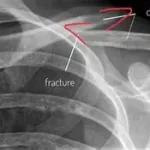

Le vomissement de sang, aussi appelé hématémèse, est un symptôme impressionnant qui nécessite une réaction rapide. Qu’il s’agisse de sang rouge vif, de caillots ou d’un liquide brunâtre ressemblant à du marc de café, ce signe ne doit jamais être pris à la légère. Découvrez les bons réflexes à adopter pour protéger votre santé ou celle d’un proche.

La couleur et la quantité du sang donnent des indications sur l’urgence. Un sang rouge vif indique une hémorragie récente et active, tandis qu’un aspect brun foncé peut traduire un saignement plus ancien.